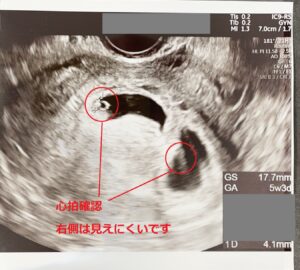

Web初めての妊娠判明、想像もしていなかった私のおなかの中には小さな2人の赤ちゃん。 一卵性双胎の妊娠〜出産までの体験談を紹介します。 目次 ・妊娠判明から双子と知るまで ・するWeb 二卵性双子のエコー写真5週~29週公開&双子4Dエコーの疑問を解決! 22年12月11日 「双子ってエコーで2人同時に見えるの? 」 これ、よく聞かれました。

Incoming Term: 妊娠初期 双子かも, 妊娠初期 双子 兆候, 妊娠初期 双子 エコー写真,